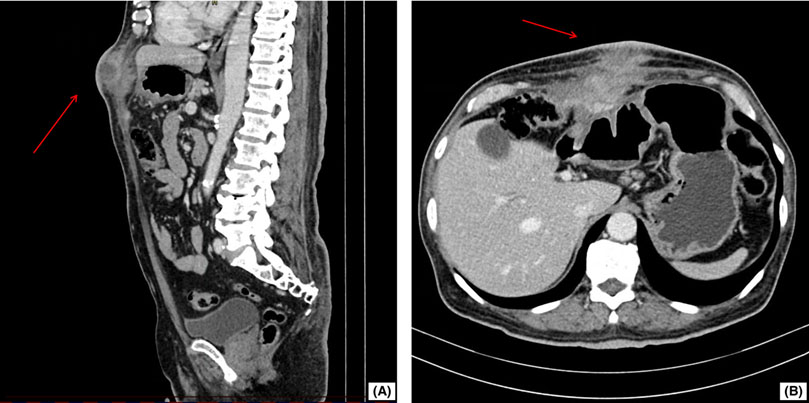

Initial studies included a computed tomography (CT) scan of the abdomen (Figure 1), which showed focal thickening of the transverse colon accompanied by an ill-defined inflammatory lesion extending towards the abdominal wall and a collection suggestive of a colo-cutaneous fistula. This raised the suspicion of a neoplastic process. The contrasted thoracic CT scan showed no alterations. Relevant laboratory tests are presented in Table 1. Helicobacter pylori testing was not performed at the time of admission.

Figure 1 Abdominal CT Scan in Sagittal and Axial Views. (A) Sagittal View of the Abdomen: The imaging reveals a clear and distinct heterogeneous-density soft tissue mass (marked with a red arrow) in the abdominal wall extending toward the cutaneous surface. (B) Axial View of the Abdomen: A soft tissue mass (red arrow) adherent to visceral structures is visualized and consistent with multiorgan adhesions.

This case presents a unique diagnostic challenge where actinomycosis mimicked malignancy, requiring careful evaluation of our diagnostic approach and differential diagnosis. Our patient's presentation with a painful, indurated epigastric mass with cutaneous involvement and constitutional symptoms strongly suggested neoplasia, particularly given the CT findings of a heterogeneous mass with multiorgan adhesions.

Regarding our diagnostic workup, we followed established protocols for suspected abdominal masses. The CT imaging showed characteristic findings that could be consistent with either infectious or neoplastic processes 7. Computed tomography findings in actinomycosis include the formation of abdominopelvic abscesses, bowel wall thickening, inflammatory infiltration of the pericolic fat, and mass lesions, which can mimic neoplastic processes 8. The diagnosis frequently requires biopsy and histopathological identification of the organism 9, as well as microbiological studies to confirm the presence of Actinomyces spp. For Helicobacter pylori detection specifically, tissue biopsy and biochemical tests on bacteria isolated from biopsy samples have shown superior diagnostic accuracy compared to other methods 10. The positive aerobic culture for A. shaaliae georgiae was crucial, though this initially increased rather than decreased our suspicion of malignancy, as co-infection with neoplasms has been reported 11.